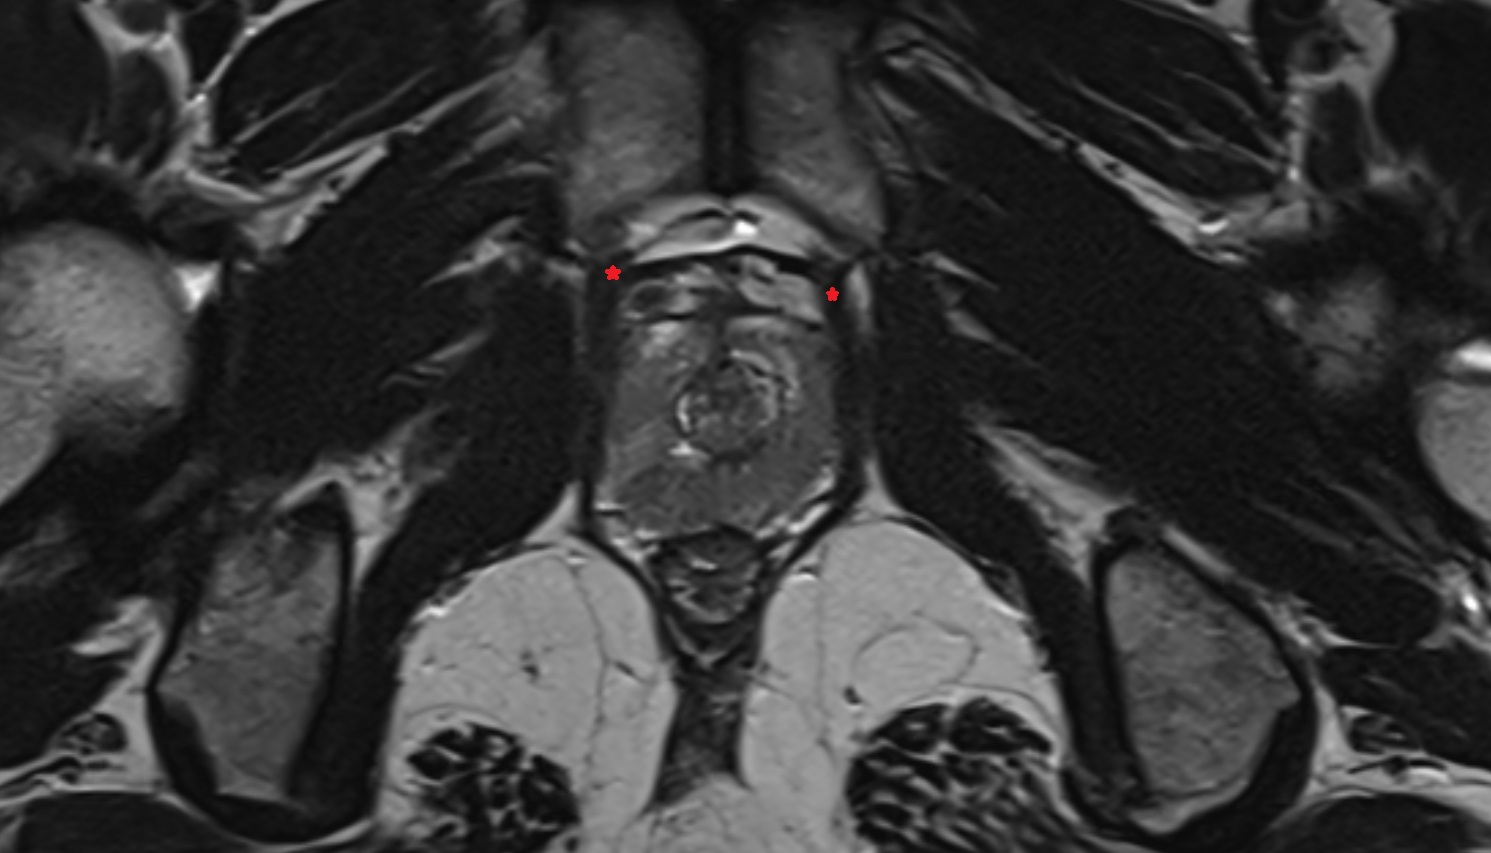

- Seminal vesicle

- Peripheral zone of prostate

- Anterior Fibromuscular Stroma of prostate

- Central zone of prostate

- Transitional zone of prostate